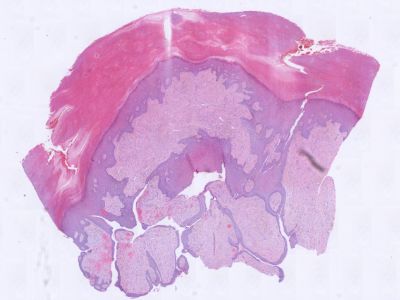

![Histologie onychomatricoma (click on photo to enlarge) [source: Kevin Kwee / Afdeling Pathologie MUMC] Histologie onychomatricoma](../../../pacoupes/thumbnails/onychomatricoma.jpg) |

ingescande coupe (zoom) |

Diagnostiek:De diagnose kan gesteld worden door het

uiteinde van de nagel af te knippen en naar de PA te sturen. In het stukje nagel

ziet men de karakteristieke gaatjes van verschillende diameter, gevuld met serum

en bekleed met een dun laagje epitheel (eventueel aan te kleuren met een cytokeratine

kleuring).